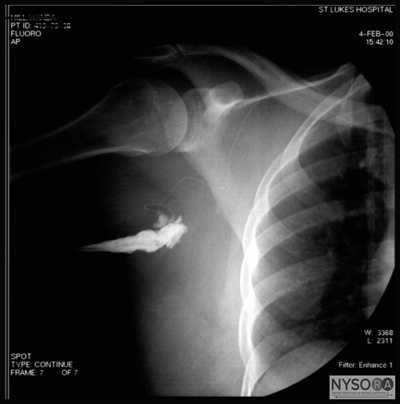

The needle insertion site is marked approximately 3 cm caudal to the midpoint of landmark 3 (Figure 7) An X-ray film demonstrates the relevant anatomy (Figure 8):

Figure 7: Needle insertion point for infraclavicular brachial plexus block. The medial and lateral circles outline the sternal head of the clavicle and coracoid process, respectively. 1. Coracoid procoess 2. Clavicle 3. Humerus 4. Scapula 5. Rib cage